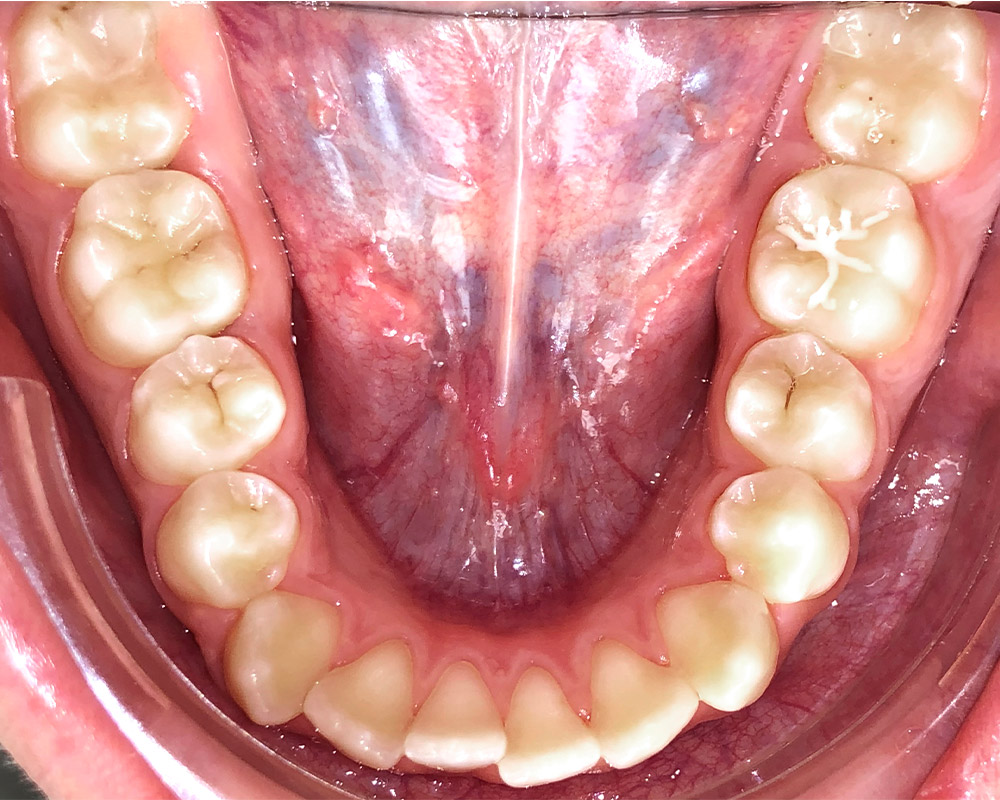

Скученность - Кейс 16

Эффективность устранения дефекта прикуса посредством элайнеров FlexiLigner.

Результаты лечения